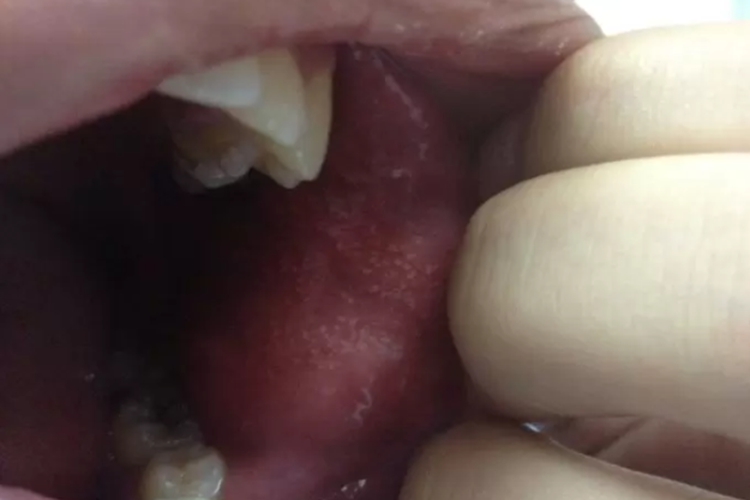

迷脂症又称皮脂腺异位症,疾病表现为黏膜或皮肤黏膜交界处淡黄色针尖大的斑疹或丘疹、皮疹稀疏分布或相互融合。根据受累部位不同分为口唇部位、颊黏膜。皮损发展到一定程度后静止,患者亦无不良感觉。